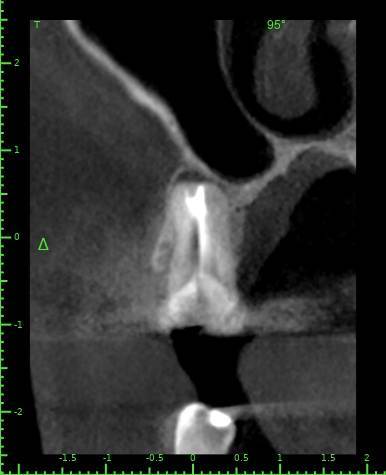

Здравствуйте, появился полгода назад свищ на десне, заполняется и лопается, затягивается и снова появляется, спустя пару месяцев обратился в стоматологию, на снимке ничего критичного не увидели, отправили домой наблюдать тип, еще прошло 3 месяца, так и не проходит и хуже не стало, болей нет никаких, только небольшая если трогать в районе свища, пойдя в другую стоматологию, сделали снимок и так же непонятно что и почему, пошел на КТ, и обратно в стоматологию, есть какая то полость, можно попробовать но нет гарантии, что пройдет, прикрепляю снимок К

ТРезультаты и плюс программа для открытия